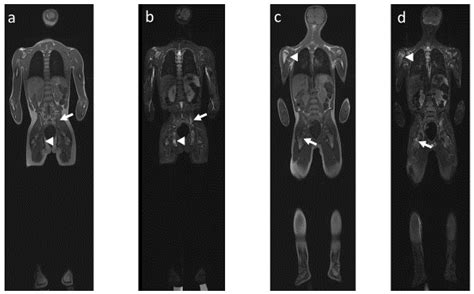

The lesions most commonly appear in the metaphyses of long bones, the pelvis, the vertebrae, and the clavicle. The "multifocal" aspect of the name refers to the fact that these lesions can appear in several locations simultaneously or develop sequentially over time, leading to a frustrating cycle of remission and flare-ups that can last for years.

Diagnostic Approach and Imaging

Diagnosing Chronic Multifocal Osteomyelitis is a process of exclusion. Because there is no single laboratory blood test that confirms the diagnosis, physicians rely on a combination of clinical findings, imaging, and, in some cases, a bone biopsy to rule out other more serious conditions like malignancy or bacterial osteomyelitis.

MRI (Whole Body) The gold standard for identifying multifocal lesions without radiation exposure.

💡 Note: A whole-body MRI is highly recommended by specialists to identify asymptomatic lesions that might otherwise go undetected.